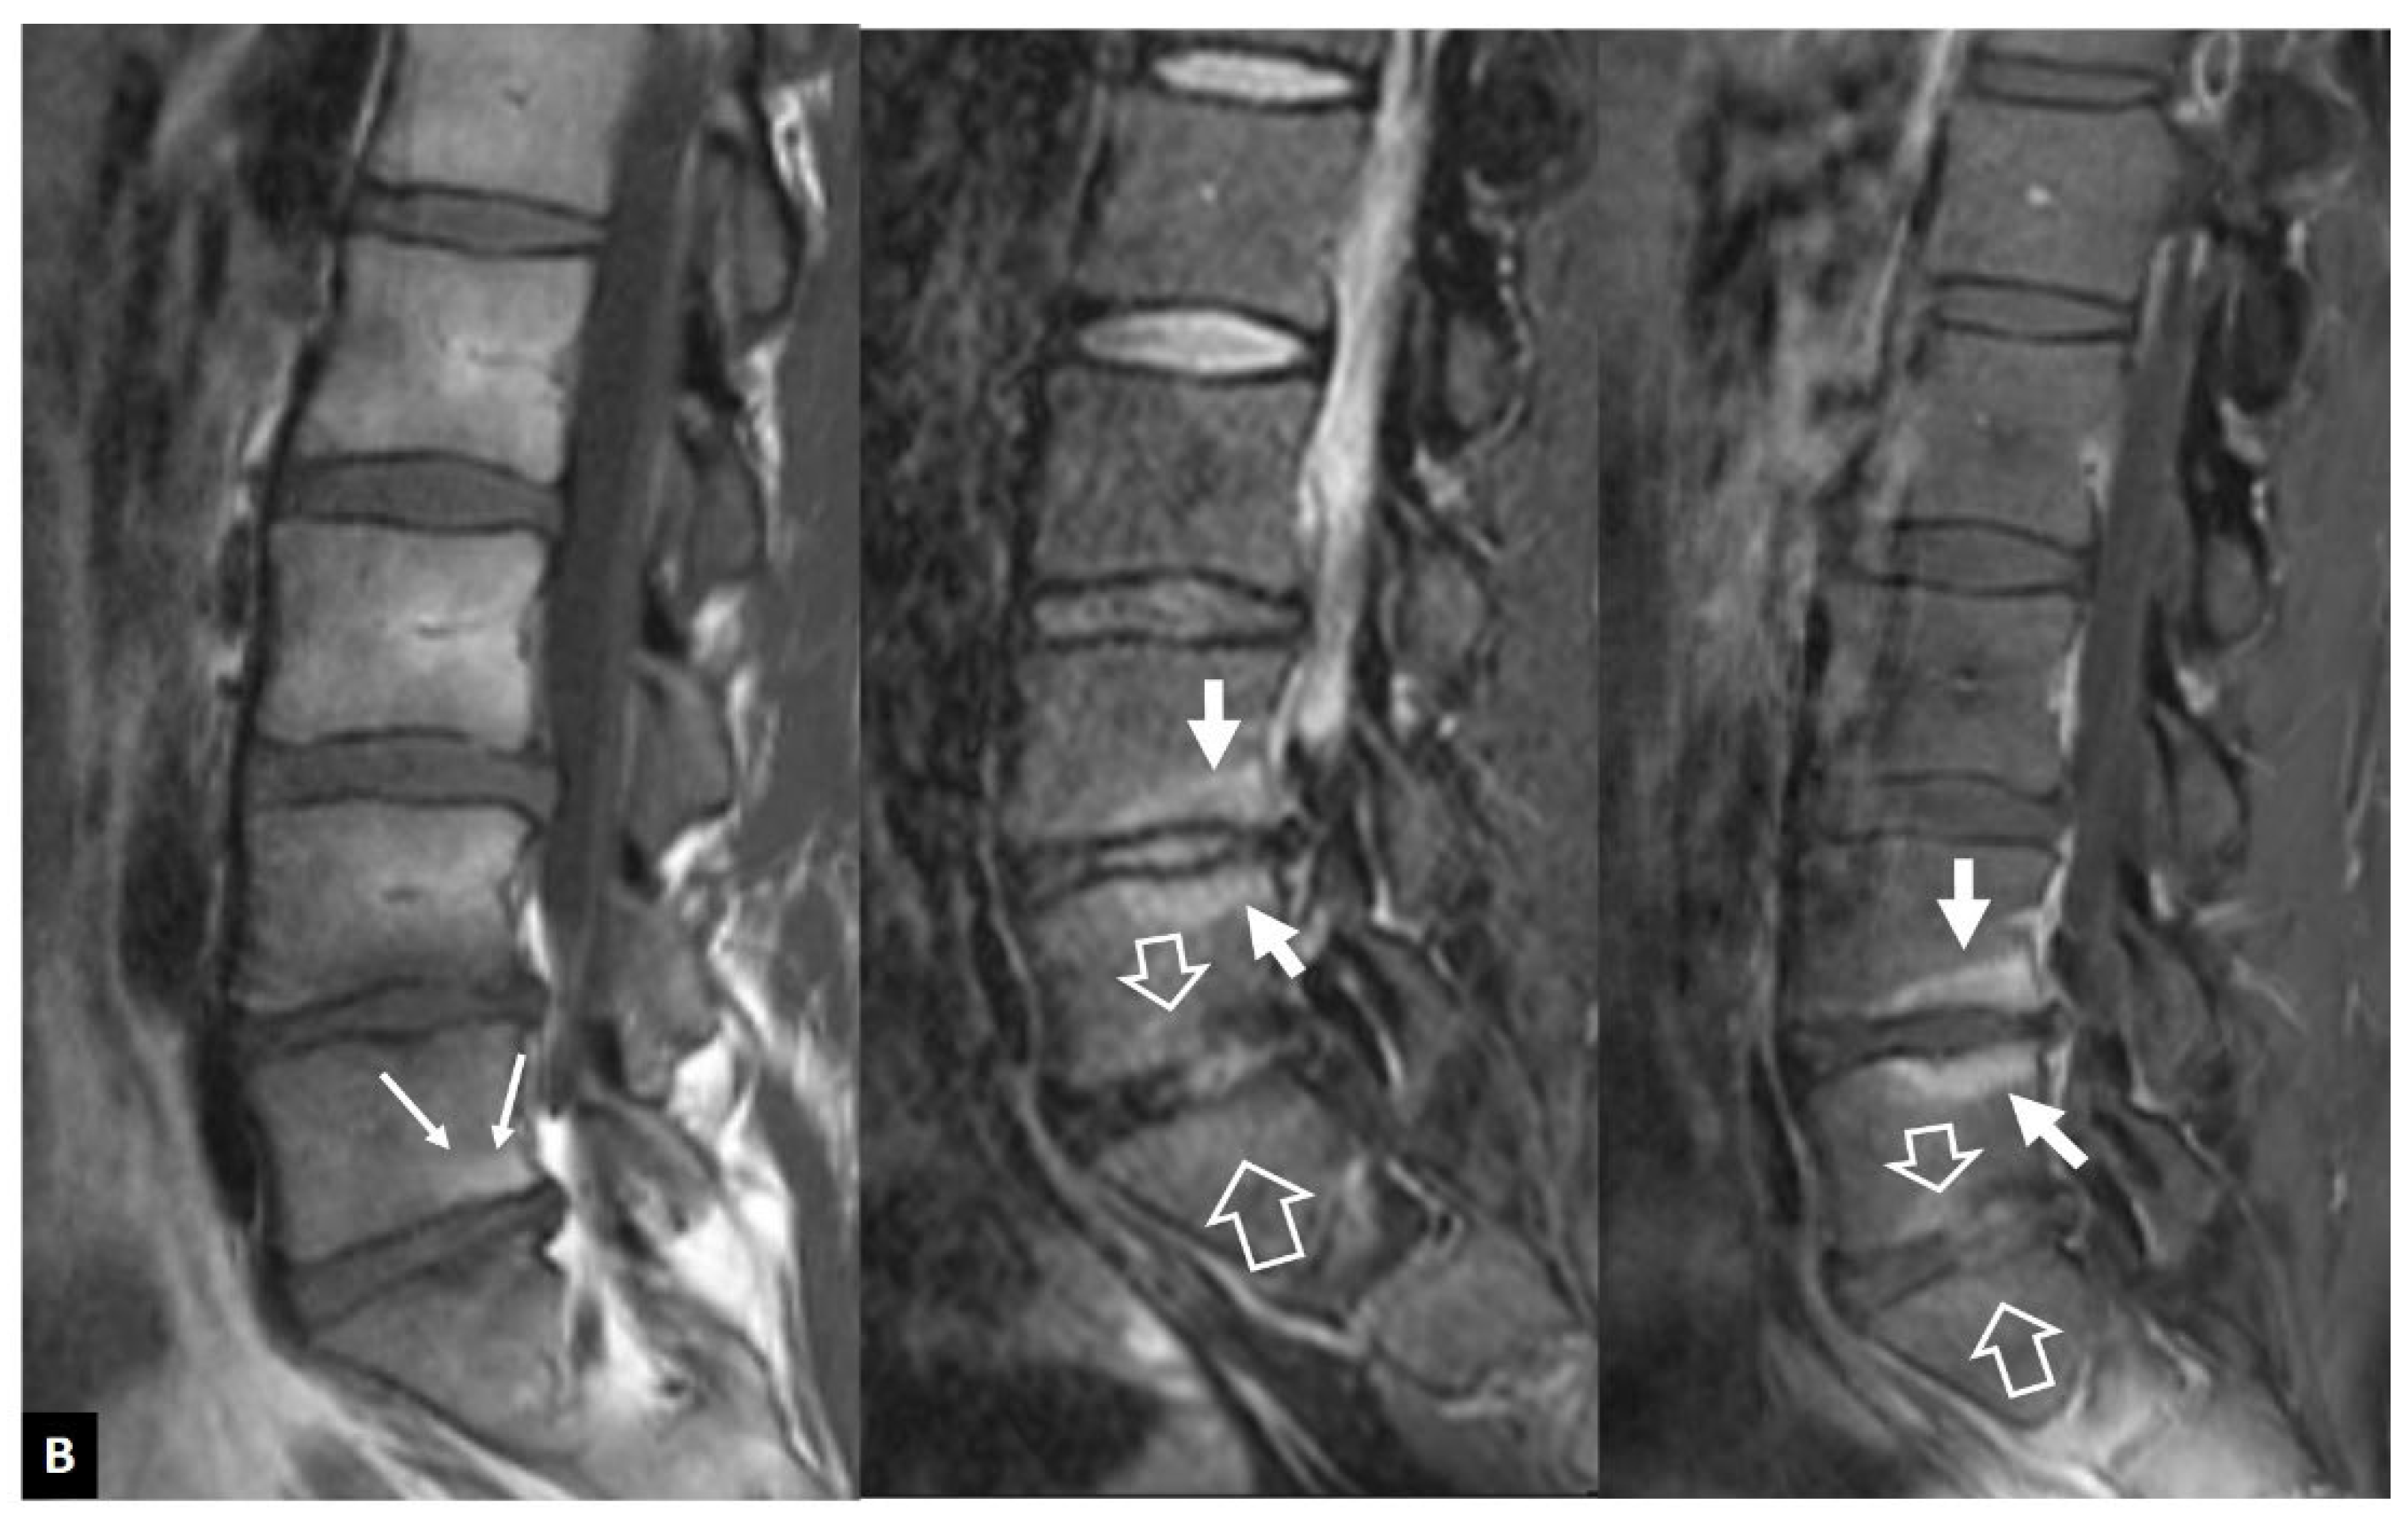

1. a.ii. Aseptic Spondylodiscitis

1. a.iii. SAPHO Syndrome

1. a.iv. Destructive Spondyloarthropathy

1. a.v. Crystal Deposition

1. a.vi. Postop Aseptic Discitis

1. a.vii. Trauma